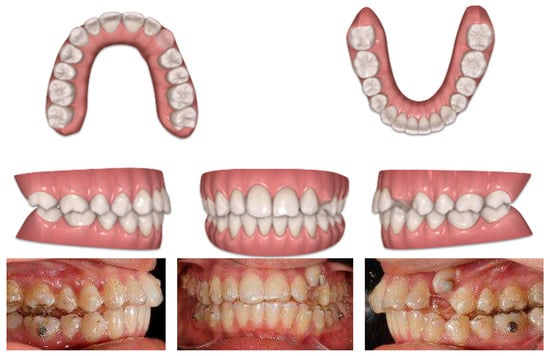

In the first Clincheck®, the use of an eruption compensator was planned in order to locate the displaced canine.

At the same time, the canine was linked to the button cutout of 36 teeth by using Class II elastics to extrude and tip it. On the right side, Class II elastics were placed in order to improve the dental Class II malocclusion (Figure 14 and Figure 15)

Figure 14.

First Clincheck® and the first set of aligners to create space and achieve the alignment and levelling of both arches. Use of elastics and buttons as auxiliaries to promote the extrusion of the impacted canine.

Figure 15.

Progress of treatment with the mechanics of elastics.

Once the displaced tooth was in a better position and near the crest, intraoral impressions and a new series of pictures were taken. Then, an upper arch expansion was planned in order to correct the transverse discrepancy and crowding.

A horizontal rectangular attachment was placed on the buccal surface of the canine, and lingual root torque was applied to ensure the three-dimensional control of the tooth movement (Figure 16).

Figure 16.

Digital impressions after the first set of aligners and a new Clincheck® to refine the occlusion.